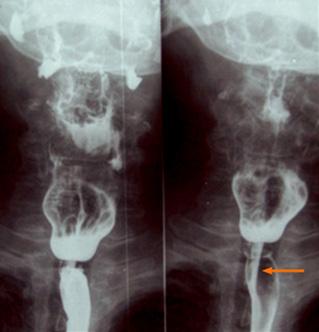

La obstrucción completa de la arteria provoca una elevación del segmento ST cóncava hacia abajo en derivaciones contiguas (> 1 mm en todas las derivaciones) . Por tanto, la localización del infarto se determina por las derivaciones, en las cuales se eleva el segmento ST:

Septal (obstrucción de ADA): V1-V2.

Anterior, incluido el ápex (obstrucción de ADA distal): V3-V4.

Lateral (obstrucción de arteria circunfleja): I, aVL (lateral alto) . V5-V6. (lateral bajo)

Anterior extenso (obstrucción de ADA proximal): V1-V6

Inferior o diafragmática (obstrucción de ADP, rama coronaria derecha): II, III aVF